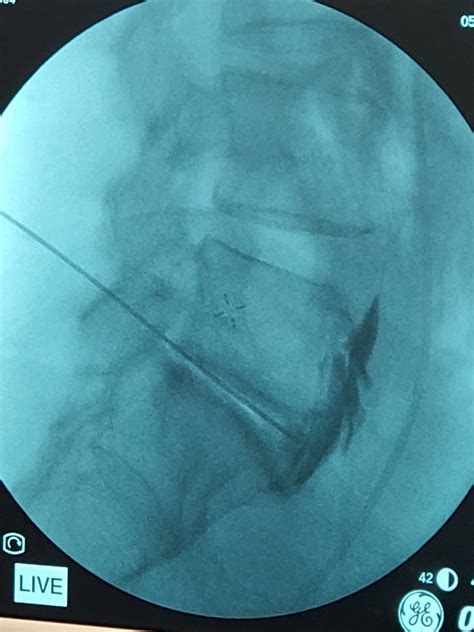

The procedure is typically performed under fluoroscopic or CT guidance to ensure accurate placement of the needle. The patient is usually positioned prone, and the needle is inserted through the skin and advanced to the target area. Once the needle is in place, the anesthetic and/or corticosteroid is injected.

• Fluoroscopy: Fluoroscopy is often used during interventional procedures to guide the placement of needles or catheters into the Superior Hypogastric Plexus.

Interventional procedures, such as nerve blocks or neurolysis, can provide targeted relief from chronic pelvic pain. These procedures are often performed under imaging guidance to ensure accurate placement of the needle or catheter.